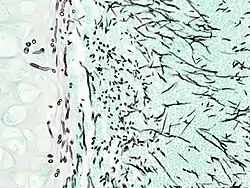

| Pulmonary invasive aspergillosis in a person with interstitial pneumonia (autopsy material), using Grocott's methenamine silver stain | |

On microscopy, Aspergillus species are reliably demonstrated by silver stains, e.g., Gridley stain or Gomori methenamine-silver.[13] These give the fungal walls a gray-black colour. The hyphae of Aspergillus species range in diameter from 2.5 to 4.5 µm. They have septate hyphae,[14] but these are not always apparent, and in such cases they may be mistaken for Zygomycota.[13] Aspergillus hyphae tend to have dichotomous branching that is progressive and primarily at acute angles of around 45°.[13]